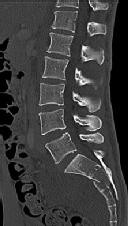

Figures 1 through 3 show the radiograph and CT images of a 68-year-old

woman who sustained a cervical injury after tripping over her cat. She has mild facial trauma, which includes a broken upper incisor and a nonsurgical nasal fracture. She is neurologically intact. Her past medical history is consistent with obstructive sleep apnea, non–insulin-dependent diabetes mellitus (hemoglobin A1c level of 9.0), and morbid obesity, with a body mass index of 40. What is the preferred treatment for this patient?

4. Anterior odontoid screw fixation Discussion: C

Posterior C1-2 fusion with instrumentation provides stability and pain relief with excellent clinical outcomes despite the loss of C1-2 motion. Hard collar immobilization and halo vest immobilization both carry a substantial risk of nonunion in this patient because of her age, fracture displacement, residual fracture gap, and medical condition. Anterior odontoid screw fixation theoretically preserves C1-2 motion. In this case, the fracture is not reduced. Concentric reduction is a requisite for osteosynthesis of the odontoid. Her body habitus also may not allow anterior odontoid fixation.